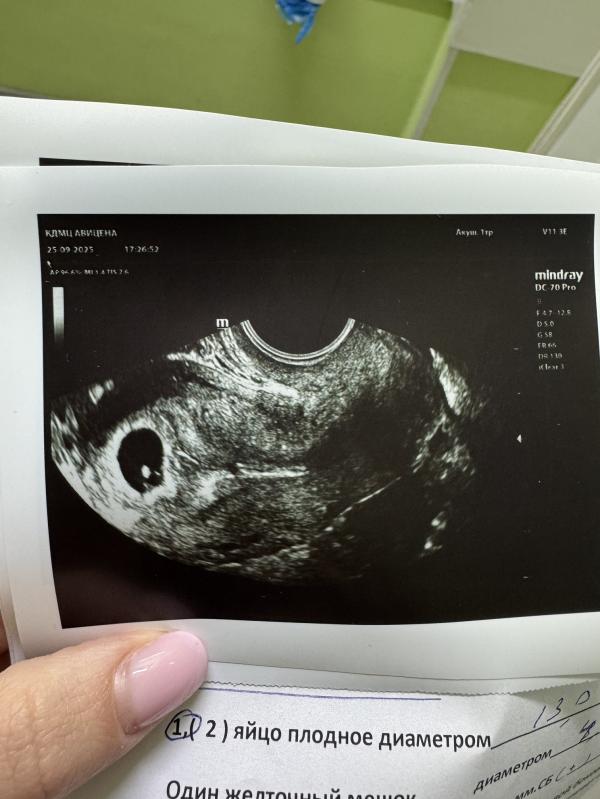

Сегодня было первое узи на акушерском сроке 5.5 недель. Эмбриональный поставили 6 недель, уже бьется сердечко, 105 ударов ❤️

Обнаружили две небольшие кисты. У кого они тоже были в начале беременности? Рассосались потом?